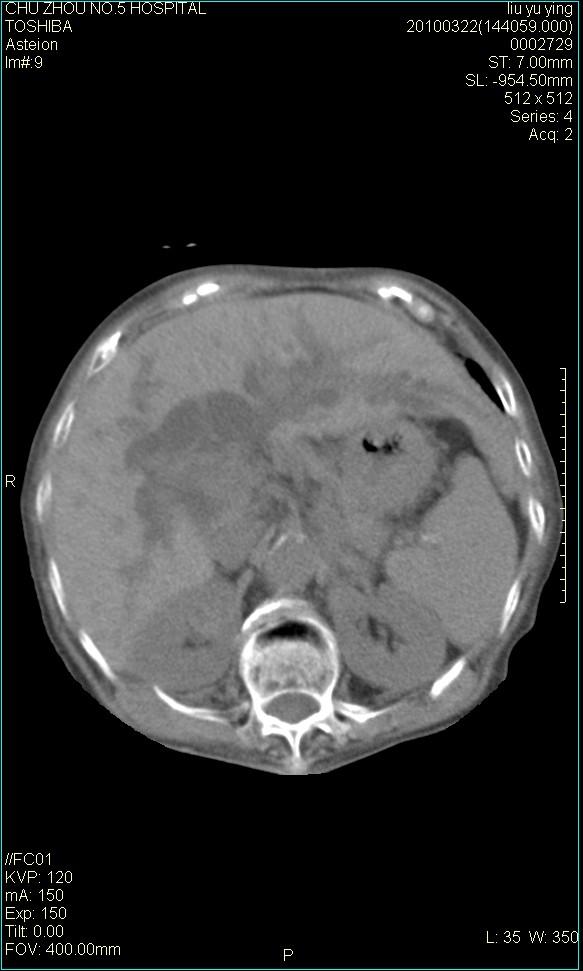

以下是引用科室第一人在2010-3-23 6:50:00的发言:[br]胆总管下段梗阻,多为肿瘤性病变,巨形胆囊,胆囊炎胆囊窝积液。[br]双侧胸腔积液,右降

以下是引用随光逐影在2010-3-23 8:12:00的发言:[br]1)胆系低位梗阻(肝内外胆管扩张,胆囊增大),原因待查。2)胆囊炎。3)双侧少量胸腔积液。4)降主动脉迂曲。